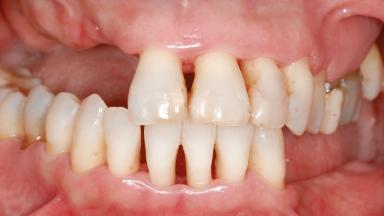

A 46-year-old woman was referred for treatment whose main complaints were mobility of her fixed partial dentures (right maxilla and left mandible) and periodontal bleeding during function. She also reported having taken systemic antibiotics to treat recurrent swelling in the area of the upper left molars. The patient had not seen a dentist for at least 2 years. She did not smoke and had no history of major systemic disease other than two minor orthopedic procedures some years back. The first-visit examination revealed poor plaque control, tooth mobility, periodontal disease, and a residual dentition widely associated with deep periodontal pockets.